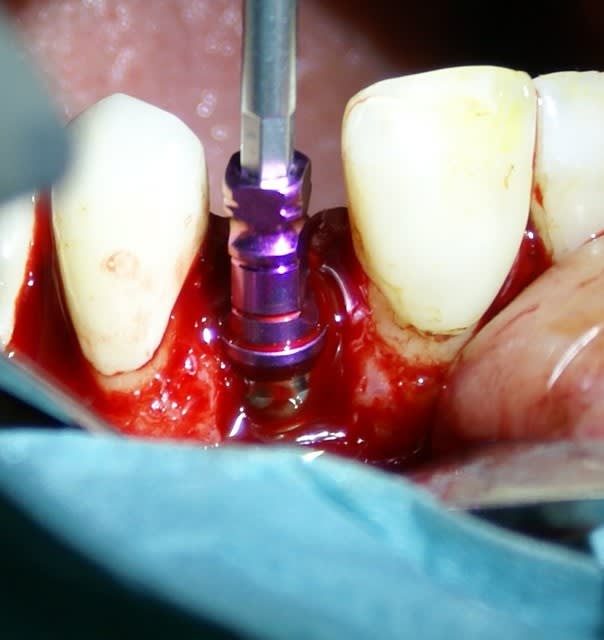

Tout à fait d'accord growler et c'est d'ailleurs ce que l'on peut voir sur le cas suivant. Fracture radiculaire, aucune infection periradicualire. Extraction et implantation immediate. Espace existant entre l'implant et l'alvéole est comblé par du BioOss. Un logement sous gingival est formé en vestibulaire et palatin de facon à pouvoir recouvrir le tout par BioGide et un conjonctif enfoui.

L'implant est de 15mm mais l'alvéole était large et 50% environ de la surface implantaire n'était en contact qu'avec du BioOss. J'ai pour cela préféré enfouir.